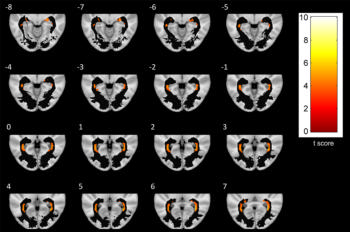

Figure 5. A series of axial-section images show white matter (WM) voxel-based morphometry analysis of posterior WM regions. Statistically significant reduction in clusters of WM concentration is shown in patients with Parkinson disease. Only clusters comprising at least five suprathreshold voxels and involving optic radiation (OR) were included in analysis and are shown in the figure. To help visualization, OR mask was visualized as a black region of interest.